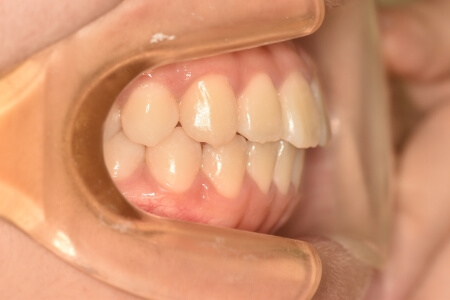

動的治療終了時

症例 症例 症例 症例 症例

治療としては、非抜歯の上、マウスピース型矯正装置(インビザライン)で配列を行いました。顎間ゴムの協力もあり、開咬、中心のズレがきれいに改善されました。

治療期間は、2年でした。